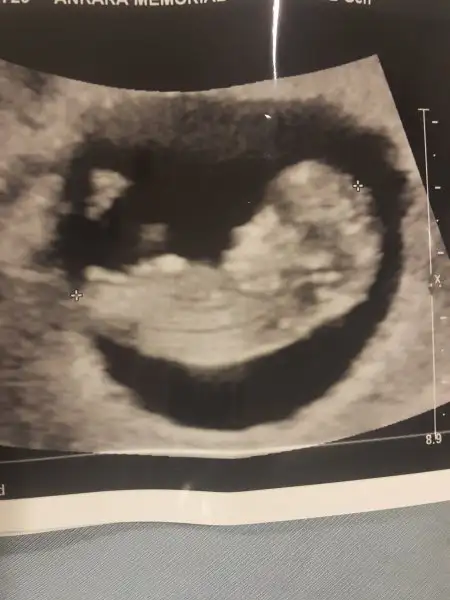

Doktor önce kıza benziyor dedi sonra çıkıntı gibide duruyor.kesin birşey diyemem dedi.acaip merak ediyorum

o çıkıntı bu haftada hepsinde oluyor ya o yüzden emin olamamıştır canım. aslında o tam olarak nub. bir resimde kesin erkek dedim, birinde ise nub paralel gibi geldi o yüzden emin olamadım.

Bu nubta benim kafamı karıştırıyor nubu paralel benim fasulyenin, ama cıkıntı şeklinde görüldü ultrasonda bacak arası olarak. 11+0 da gittim. Erkek olacak galiba diyorum ama nub olayıda kafamı karıştırıyor. Bak resim bu paralel dimi?

11-12.haftalardaki çıkıntı pipi değil canım, nub çok net olarak :) bana kız gibi geldi bu resimde. ne güzel heyecanlar di mi :)

Evet ben en başindan beri kutumda erkek hissediyorum ama bu resim kafamı karıstıridi nub çok net sitelerdede karşılaştırdim herkes kız nubu demiş.bide oğlum var ya daha 14 aylık nedense ona erkek arkadaş olsun istiyorum bide kıyafet masrafı yok tabi hatta 3 çocuk büyür